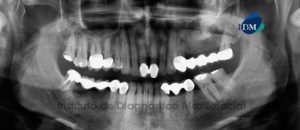

Paciente femenino, de 73 años de edad es referido al Instituto de Diagnóstico Maxilofacial (IDM) por motivos prostodónticos. La paciente es edéntula parcial bimaxilar la